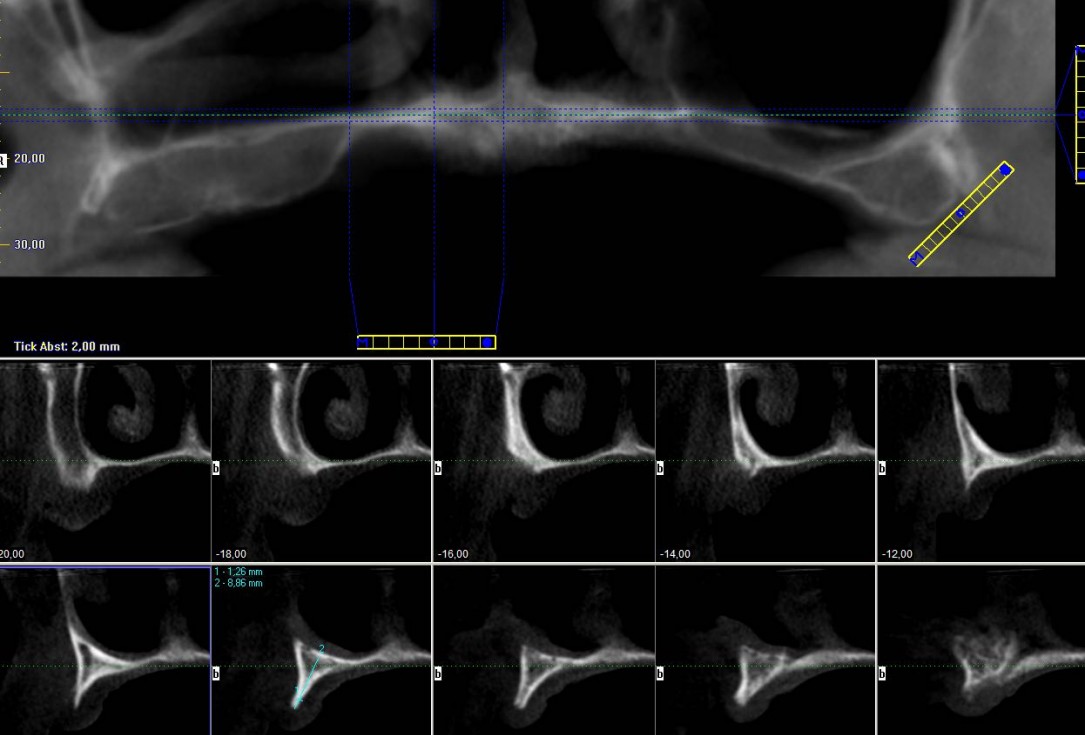

2/23 - Preoperative radiological situation – severely atrophic maxilla

Full arch reconstruction of the maxilla with maxgraft® bonebuilder - Dr. M. Erbshäuser

3/23 - Preoperative radiological situation – severely atrophic maxilla